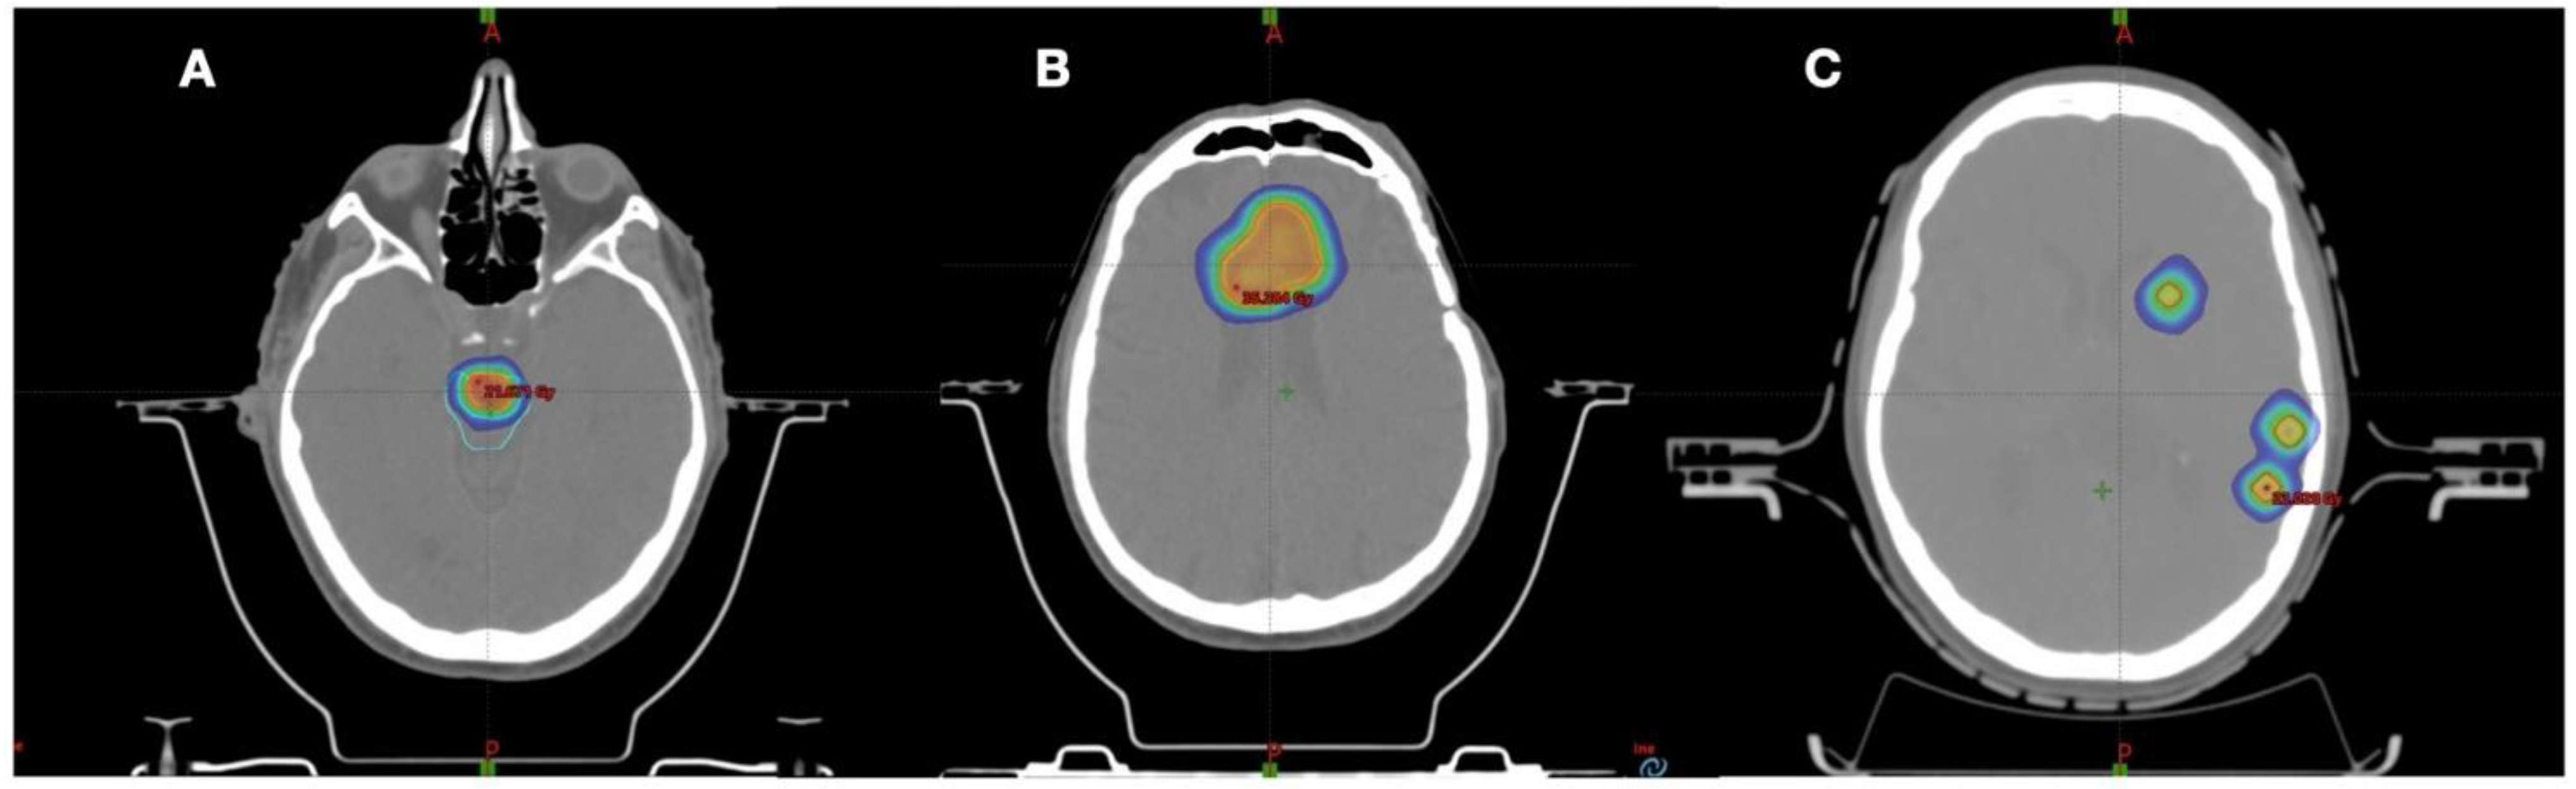

- Alongi, F.; Fiorentino, A.; Gregucci, F.; Corradini, S.; Giaj-Levra, N.; Romano, L.; Rigo, M.; Ricchetti, F.; Beltramello, A.; Lunardi, G.; et al. First Experience and Clinical Results Using a New Non-Coplanar Mono-Isocenter Technique (HyperArcTM) for Linac-Based VMAT Radiosurgery in Brain Metastases. J. Cancer Res. Clin. Oncol. 2019, 145, 193–200. [Google Scholar] [CrossRef]

- Gregucci, F.; Bonaparte, I.; Surgo, A.; Caliandro, M.; Carbonara, R.; Ciliberti, M.P.; Aga, A.; Berloco, F.; De Masi, M.; De Pascali, C.; et al. Brain Linac-based Radiation Therapy: “Test Drive” of New Immobilization Solution and Surface Guided Radiation Therapy. J. Pers. Med. 2021, 11, 1351. [Google Scholar] [CrossRef] [PubMed]